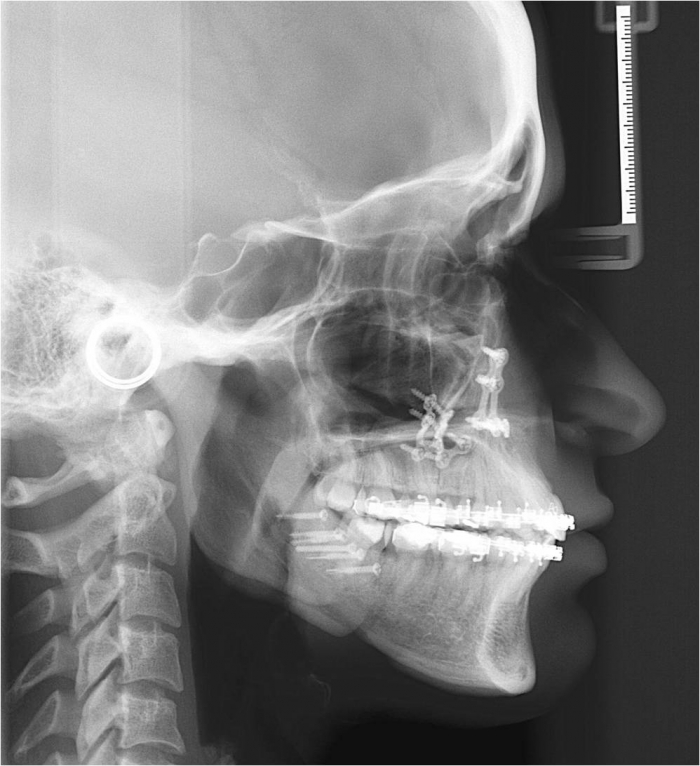

Telerradiografia inicial

Telerradiografia após a cirurgia